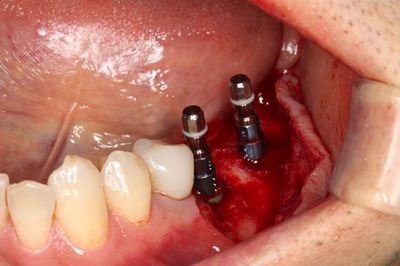

インプラントはスイスのストローマンインプラントを用います。

あくまでも個人的な意見ですが、ライバル不在とも言える優れたインプラントだと思います。

無事に2本のインプラントの埋入を終えました。

トランスファージグを取り外しました。

ヒーリングスクリューH0.5mmでスクリューホールを保護します。